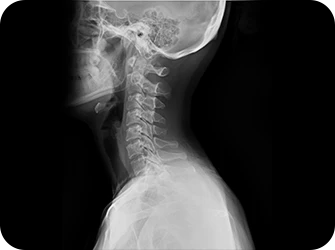

목(경추)

Neck

목디스크와 경추관협착증

질환별 차이점은?

목디스크

말랑말랑한 연골 조직인 디스크가 퇴행되거나 오랜 시간 압력을 받아 밀려나와 목 뒤를 지나는 신경을 눌러 신경손상과 함게 팔, 어깨, 손 등에 통증 및 마비 증상이 나타나는 질환입니다.

경추협착증(퇴행성)

척추관이란 척추 중앙에 터널처럼 나 있는 파이프 구조를 말하고, 안이 비어있어 뇌로부터 팔다리까지 신경이 지나가는 통로가 됩니다.

추간공이란 추골과 추골 사이에서 척수 신경이 빠져나오는 공간을 뜻합니다.

이러한 척추관 또는 추간공이 좁아져서, 신경이 지나가는 통로가 눌리면서 경추의 통증을 유발하고, 여러 복합적인 신경증세를 일으키는 질환입니다.

이제는 하세요!

엑스레이 검사

CT 검사

MRI 검사